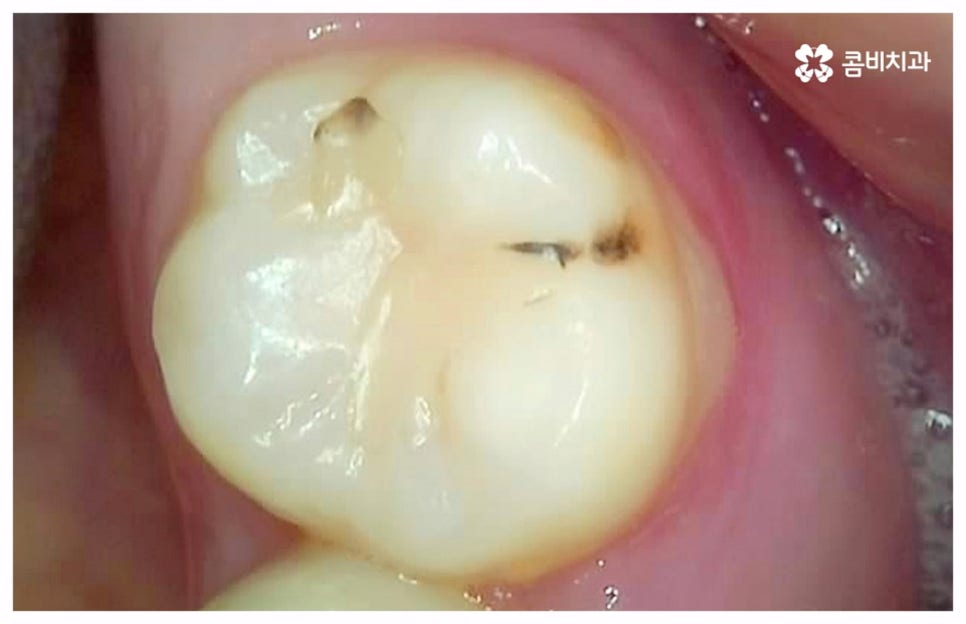

출처 아카이브 열기치통의 원인은 굉장히 다양한데 그 중 가장 대표적인 것으로는 구강 질환과 치아파절을 생각해 볼 수 있을 거예요. 충치나 잇몸병과 같이 구강 내부 상황으로 인해 발생하는 것이 구강 질환이라면 외부에서 충격을 받아 치아가 부러지거나 깨지는 것을 치아파절 이라고 할 수 있는데요. 이렇게 내적 또는 외적인 원인으로 생긴 치아 손상은 자연적으로 낫지 않으며 시간이 지날수록 빠르게 악화되기 때문에 구강 질환이 발생했거나 치아가 파절되었을 때 시기를 늦추지 말고 바로 치과에 내원하셔서 꼼꼼하게 검진을 받고 상황에 적합한 치료를 받으실 필요가 있습니다.

충치나 잇몸 질환은 보통 단계적으로 서서히 발전하기 때문에 환자분들께서 하루 아침에 극심한 통증을 느끼게 되는 경우는 많지 않지만 혹시라도 갑작스럽게 치통이 심할때 혹은 밤에 자려고 누웠는데 더욱 치통이 심할때 는 급성치수염을 의심해 볼 수 있어요. 급성치수염은 언급했던 충치나 외상성 치아 파절로 인해 치아 가장 안 쪽에 있는 치수 부분까지 세균이 침투하여 염증이 발생하는 것을 의미하는데, 이 때 감염된 혈관이 부어오르면서 단단한 치아 외벽에 둘러쌓인 치아 내부 압력이 올라가 작은 움직임에도 극심한 통증을 느끼게 되는 거예요.

급성치수염에 대한 치료는 보통 안쪽까지 침투한 세균을 깨끗하게 긁어내고 염증 및 괴사된 치수 부분을 삭제한 다음 뿌리관(근관)을 소독하고 치과 충전물로 밀봉하는 신경 치료를 통해 이루어지는데, 이렇게 신경 치료를 진행하고 나서 후속 치료로서 남아있는 자연 치아를 보호하고 저작 기능을 제대로 수행할 수 있도록 하기 위해 주변 치아와 크기, 높이 등을 맞추어 딱 맞게 제작한 보철물을 덮어씌우는 크라운 치료를 해 주는 것이 자연 치아를 보다 오랜기간 동안 건강하게 사용할 수 있도록 하는데 크게 도움이 된다고 할 수 있어요. 경우에 따라서 앞니의 경우 신경관이 많지 않기 때문에 레진으로 치료를 마무리하는 경우도 있으니 참고해 주시면 좋을 것 같아요.